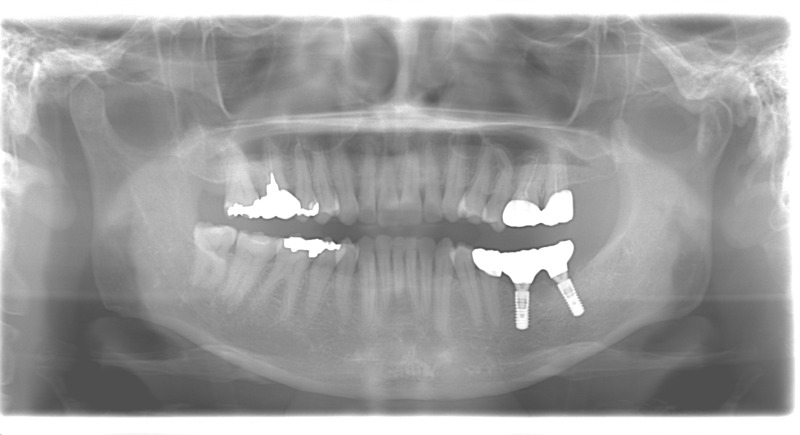

症例

50代女性のインプラント治療

担当医の処置方針

左下2本の欠損部にはインプラント治療を行いました。 矯正も希望されていたので、インプラントと矯正治療を同時に進めました。 また、不良補綴の再製も行い、理想の咬合平面となりました。

After

After

担当医師コメント

田中千恵

インプラント埋入オペ前に矯正治療も含めたシミュレーションを行い、さらにインプラント埋入ガイドを用いたので、より正確な治療計画とオペ時間の短縮が可能となりました。 インプラント埋入後の固定待機の期間中も矯正治療を並行して行うことで、トータルの治療期間を短縮することができました。